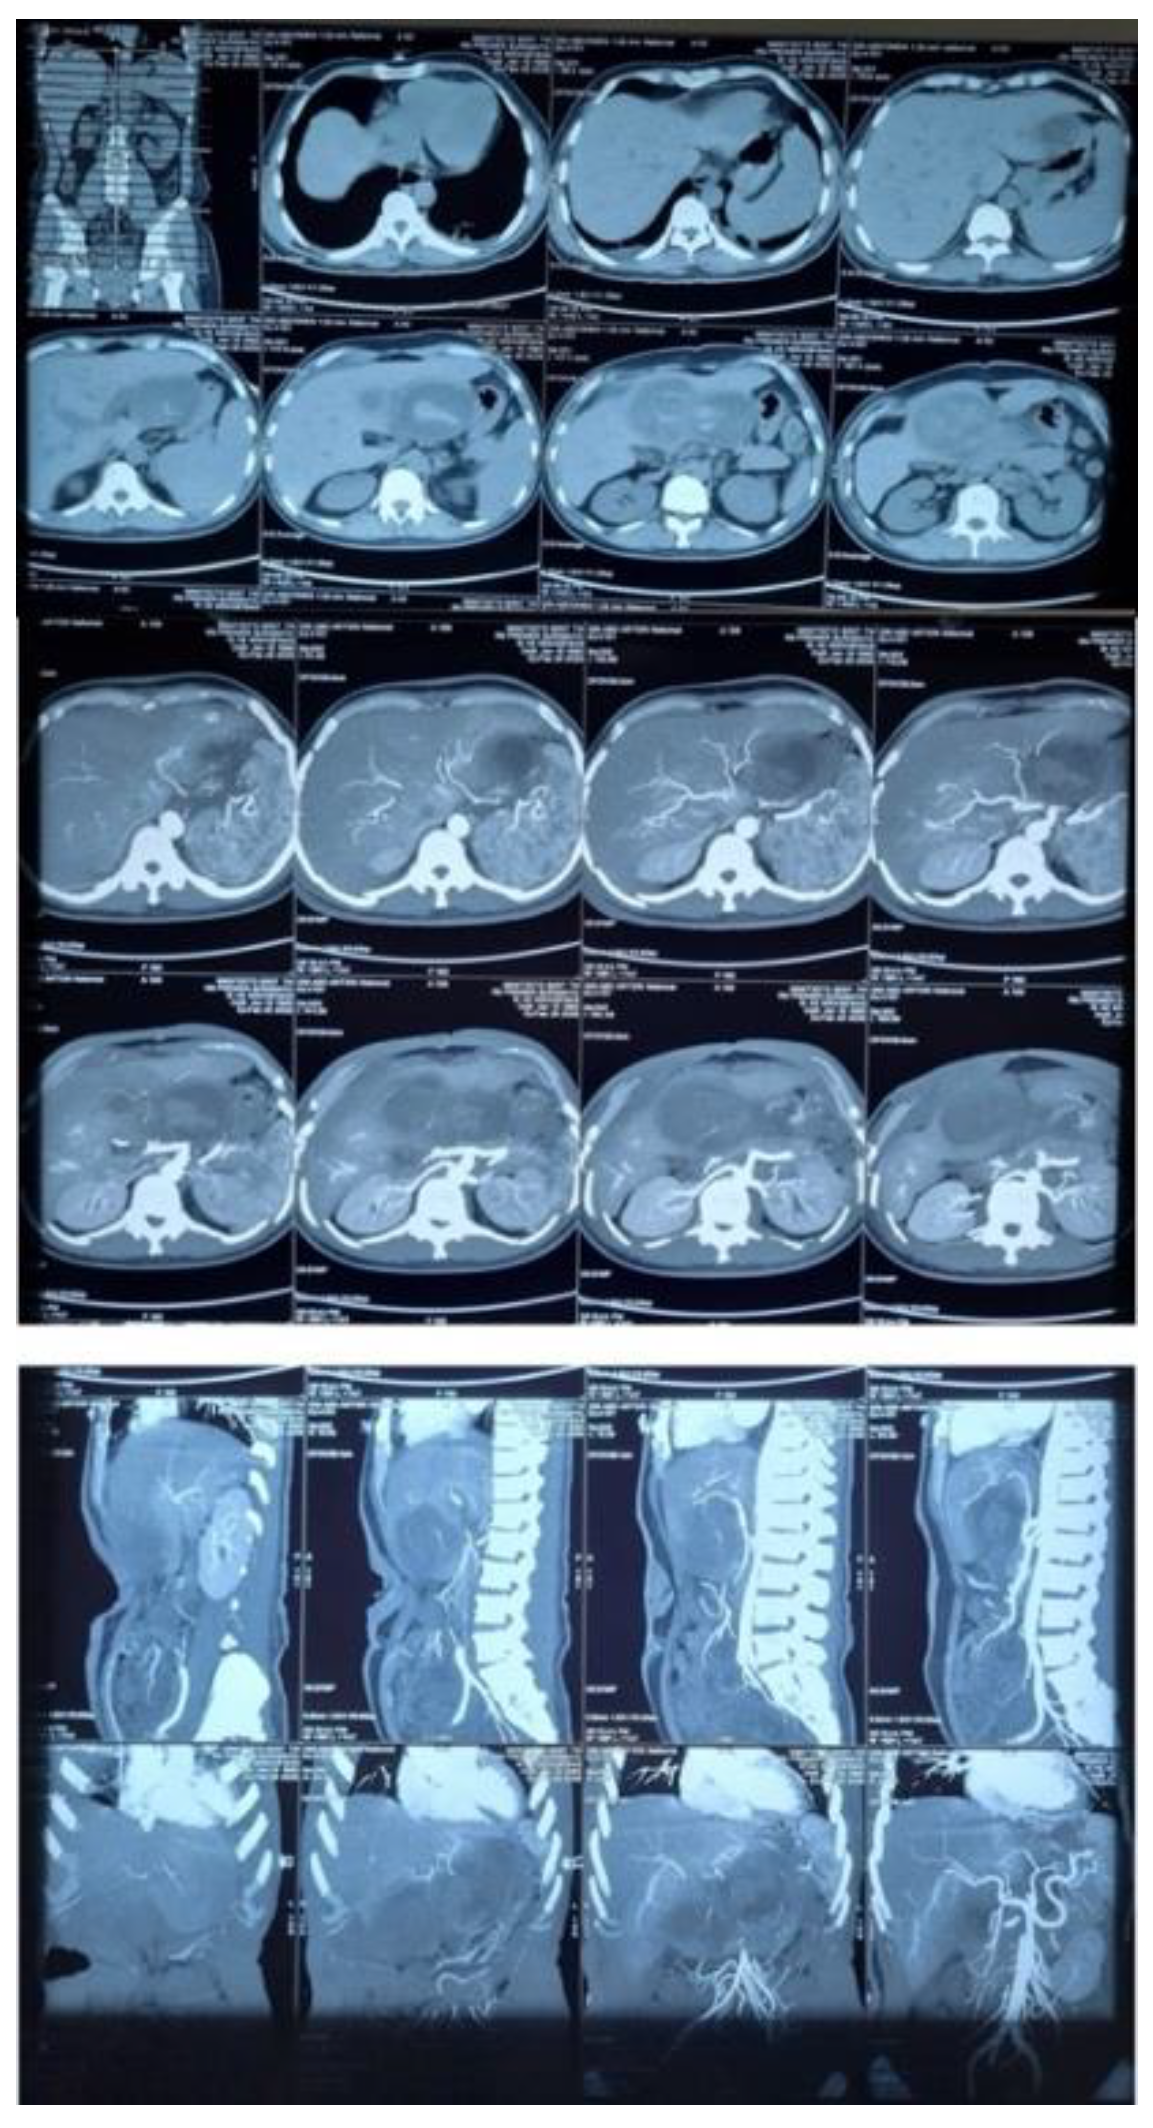

Background: Liver abscesses represent an atypical yet potentially life-threatening complication of bacterial, fungal, protozoal, and helminthic infections. Frequently, the clinical findings associated with liver abscesses are nonspecific, necessitating a reliance on imaging for diagnosis. It is uncommon for a liver abscess to radiographically resemble a malignant liver tumor such as hepatocellular carcinoma (HCC). Here, we present the case of a 45-year-old male who was initially diagnosed with HCC (BCLC C) but was subse-quently found to have a liver abscess following biopsy. Case Presentation: A male patient, 45, presented with stiffness and pain in the right upper abdomen. He complained of nausea and vomiting since 10 days before admission as well. All supportive imaging suggested a diagnosis of HCC. A liver abscess was detected during a biopsy. A liver ultrasound-guided FNAB showcased chronic, suppurative in-flammation with negative acid-fast bacilli on Ziehl-Neelsen staining. The patient sub-sequently developed a complication of middle hepatic artery bleeding and underwent immediate embolization. Discussion: In fact, a liver abscess can be the initial manifestation of HCC. Patients tend to have a poorer prognosis because the diagnosis of a liver abscess often delays the discovery of the underlying HCC. Radiographically, liver abscesses range from well-circumscribed cystic lesions with an enhancing rim to heterogeneously enhancing mass-like lesions, which are sometimes indistinguishable from liver neoplasms. However, it is so scarce that a liver abscess may radiographically mimic HCC. Conclusion: Assessing liver abscess is somewhat complicated since the symptoms vary a lot. Therefore, a correct and exact diagnosis entail a combination of more comprehensive clinical and supporting examinations.